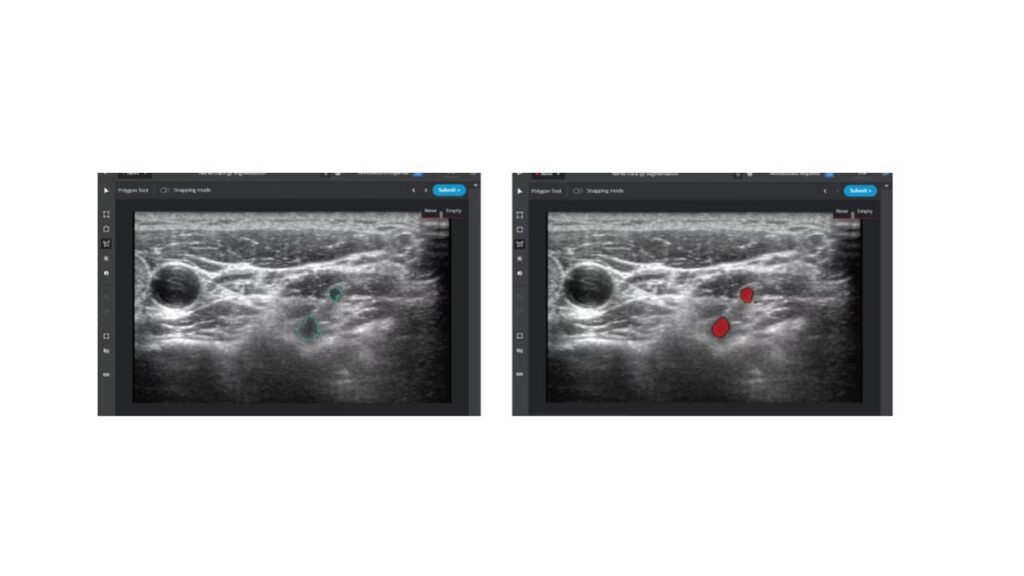

The image on the left represents ground truth, the target of the NerveTrack machine learning model. The image at right is annotated with the Intel Geti platform for inference model training proof of concept, based on 13 annotated ultrasound images.